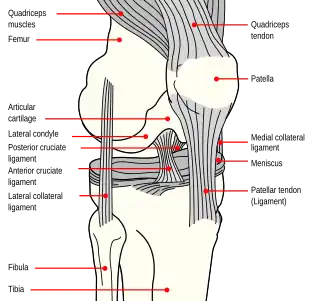

Anatomy of the knee

The patella is a triangular sesamoid bone that is embedded in tendon. It rests in the patellofemoral groove, an articular cartilage-lined hollow at the end of the thigh bone (femur) where the thigh bone meets the shin bone (tibia). Several ligaments and tendons hold the patella in place and allow it to move up and down the patellofemoral groove when the leg bends. The top of the patella attaches to the quadriceps muscle via the quadriceps tendon,[2] the middle to the vastus medialis obliquus and vastus lateralis muscles, and the bottom to the head of the tibia (tibial tuberosity) via the patellar tendon, which is a continuation of the quadriceps femoris tendon.[13] The medial patellofemoral ligament attaches horizontally in the inner knee to the adductor magnus tendon and is the structure most often damaged during a patellar dislocation. Finally, the lateral collateral ligament and the medial collateral ligament stabilize the patella on either side.[2] Any of these structures can sustain damage during a patellar dislocation.